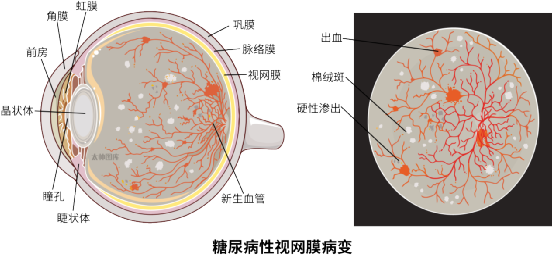

糖尿病性视网膜病变(DR)是糖尿病常见的微血管并发症,其发病情况与糖尿病患病率、病程、血糖控制等因素密切相关,全球糖尿病患者数量持续增长,预计到2045年,糖尿病视网膜病变患者将从2020年的1.03亿增至1.6亿,而并发的糖尿病黄斑水肿(DME)和增殖性糖尿病视网膜病变(PDR),是导致视力下降的最主要原因,对患者的生活质量影响巨大。

图源:太帅图库

糖尿病性视网膜病变筛查和早期治疗对于视力预后十分重要,对于2型糖尿病患者确诊时,建议同步进行首次全面眼科检查,根据眼底情况评估随访时间间隔,合并糖尿病肾病、微量白蛋白尿或肾小球滤过率下降的患者,随访间隔将缩短,且血糖波动阶段当随机复查眼底。